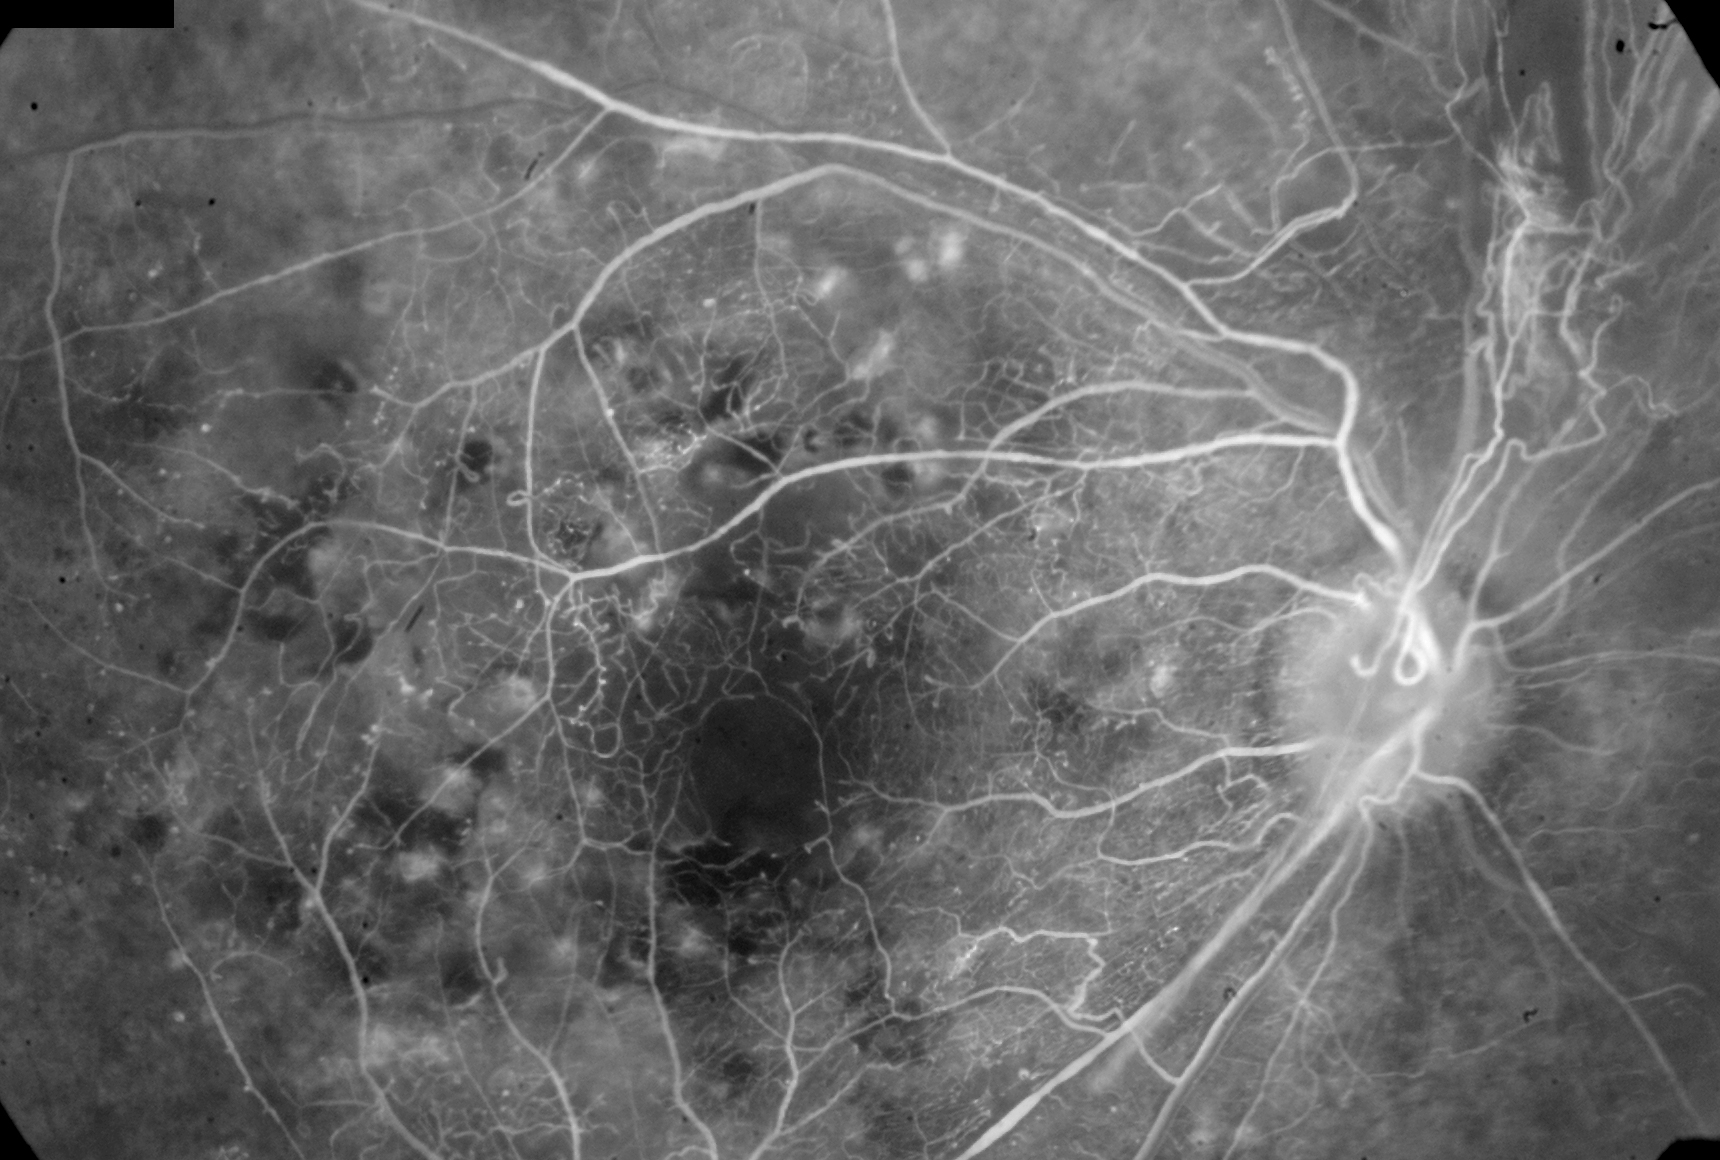

In the early 1990’s I wrote my own electronic medical record system. I also developed my own very high resolution digital fluorescein angiogram system (FA) and I started to look at the images of the diabetic patients. I became about 70% accurate in the ability to look at the FA images and tell the patient what their soda consumption was. There was focal constriction of the pre-capillary arterioles that I noticed as well as the size of the foveal avascular zone and general capillary drop out on the images. Further analysis of the electronic medical records showed a correlation of soda drinking to hypertension, renal failure and heart disease. Now as retina specialists we tend to use intraocular steroid and anti-vegf injections for these patients, while some may be reversed by a diet change of eliminating sodas first rather than having injections, with cost and the complications of drug intervention. The risk is minimal to stop the sodas, the benefit may be avoiding costly drug use and organ damage. There are multiple patients with advanced renal failure that were drinking multiple liters of diet sodas and when they quit drinking them, their renal failure progression stopped or started to reverse to the consternation of the nephrologist. The soda “quitters” had about a 10-15 point drop in the average BP without a change in the medications.